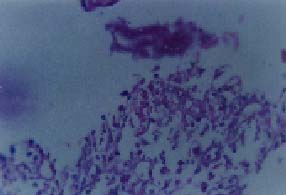

Múltiples, de 2 a 3 cm de diámetro, con fondo recubierto de fibrina entre áreas respetadas de mucosa normal en colon transverso, descendente y sigmoide. En el ciego, se observó una extensa lesión de iguales características que rodeaba la válvula ileocecal (figura 1), obstruyéndola parcialmente; la progresión del colonoscopio al íleon mostró compromiso similar en los últimos diez cm del íleon distal (figura 2), que adoptó una morfología tubular. Se tomaron múltiples biopsias en las que se observó un epitelio colónico ulcerado (figura 3) con áreas aisladas de necrosis (figura 4) que mostraron la presencia de gran cantidad de microconidias (figura 5) y que fueron confirmadas como correspondientes a HC.

Figura 5. Coloración de PAS, 100X, el mayor aumento con aceite de inmersión demuestra la presencia de microconidias de H. capsulatum (núcleo y área clara periférica por artificio).